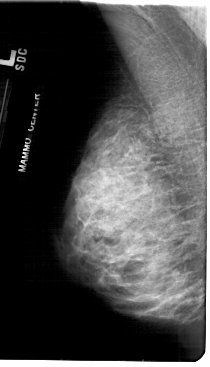

A_1845_1.LEFT_CC

LEFT_CC LINES 5326 PIXELS_PER_LINE 2971 BITS_PER_PIXEL 12 RESOLUTION 43.5 NON_OVERLAY